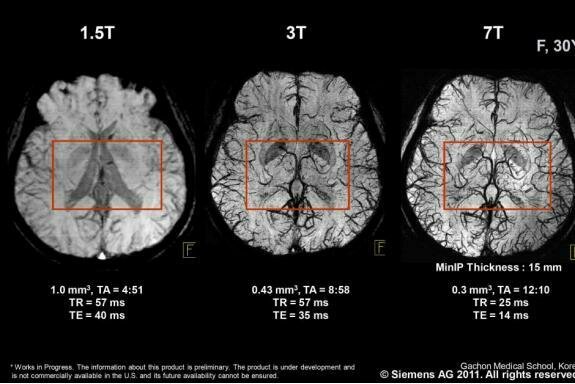

NÖROPROTEZ

Chen et al. (2023)